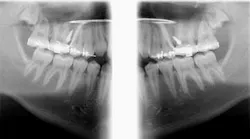

Case report

A healthy 15-year-old male presents to the clinic with an anterior open bite. His case is outlined in the figures below.

The patient in the above case report is still in active treatment. Now that successful maxillary posterior intrusion has been accomplished, the remaining full, fixed orthodontic appliances can be placed. The TPA can be removed and the molar intrusion will be held for the remainder of treatment with a ligature tie placed from the first molar to the TADs. The TADs will be kept in place for the remainder of treatment to maintain the stability of the intrusion as bone remodeling occurs.